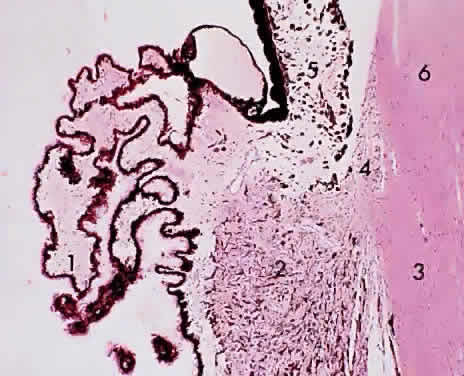

The pars plicata features approximately 80 radially placed ridged fronds representing the ciliary processes or crests (Fig. 10). The ciliary processes begin at the posterior border of the iris root and protrude into the posterior chamber. The processes have a vascularized connective tissue core covered by two layers of epithelium: a surface, nonpigmented, “secretory” cuboidal epithelium and an underlying pigmented epithelium layer (Figs. 11 and 12). The pigmented epithelial cells and the nonpigmented epithelial cells of the ciliary body are arranged apex to apex. The basement membrane of the pigmented epithelium faces the ciliary body stroma, whereas the basement membrane of the nonpigmented epithelium (internal limiting membrane) lines the posterior chamber and faces the vitreous and lens. During secretion of aqueous, nutrients from the capillaries in the ciliary processes pass through the endothelium and the basement membrane into the stroma, through the basement membrane of the pigmented epithelium to the pigmented epithelial cell, to the nonpigmented epithelial cell, and finally through its basement membrane (which forms the internal limiting membrane of the ciliary process). Tight junctions between the pigmented and nonpigmented epithelial cells inhibit leakage of nutrients between the cells. Aqueous humor formation is induced by active “secretion” by the inner cell layer (probably associated with the endoplasmic reticulum and the Golgi apparatus). Zonulae occludentes adjacent to the apical borders of the nonpigmented epithelial cells fill the lateral intercellular spaces to preserve the blood-aqueous barrier of the ciliary body.

Fig. 10. Ciliary body/pars plicata: 1, ciliary process; 2, ciliary muscle (radial and circular); 3, sclera; 4, anterior chamber angle trabecula; 5, iris; 6, cornea (× 105, KEI 8982B).

Fig. 11. Ciliary processes: 1, capillary; 2, nonpigmented (secretory) epithelium; 3, pigmented epithelium (× 195, KEI 8982B).

Fig. 12. Ciliary process epithelium:1, nonpigmented epithelium; 2, pigmented epithelium (× 580, KEI 8982B).